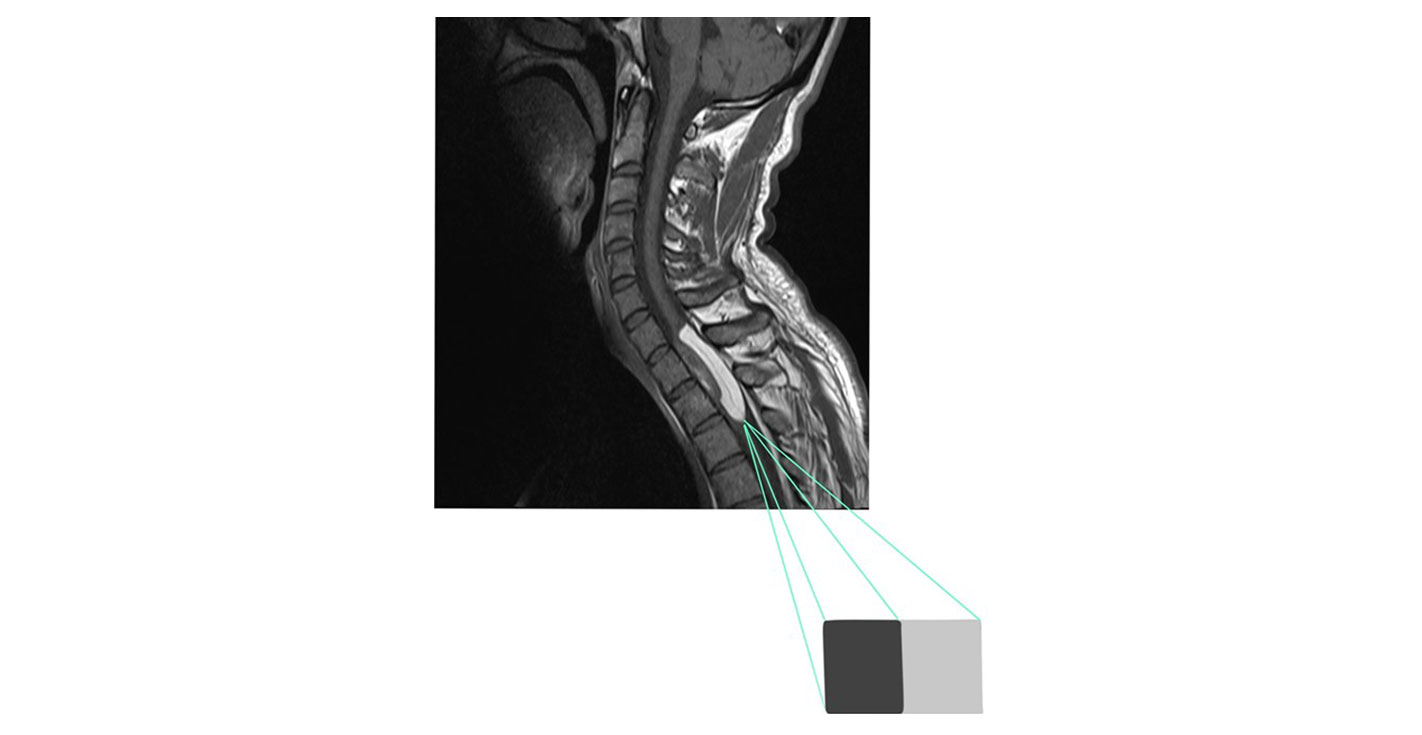

Ο λόγος αντίθεσης προς θόρυβο (CNR) συνδυάζει τον λόγο σήματος προς θόρυβο (SNR) με την αντίθεση και είναι ο λόγος της διαφοράς στην ένταση του σήματος δύο ιστών προς τον θόρυβο του υποστρώματος. Ο λόγος CNR επηρεάζεται από τις ίδιες παραμέτρους που επηρεάζουν και το SNR και είναι πολύ σημαντικός παράγοντας ποιότητας εικόνας, αφού χωρίς υψηλό CNR δεν είναι εύκολος ο ανατομικός διαχωρισμός δύο ιστών ή/και η ανάδειξη της παθολογίας.